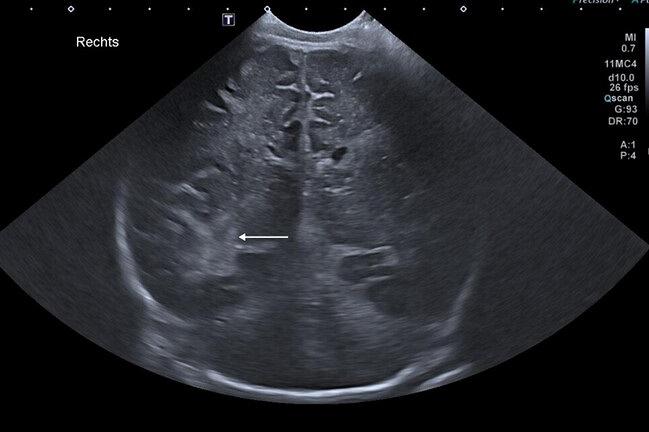

Het is essentieel om neonatale epileptische aanvallen snel te herkennen zodat de oorzaak kan worden achterhaald en de juiste behandeling direct kan worden opgestart. Het herkennen van epileptische aanvallen bij neonaten is echter lastig vanwege de diverse klinische presentaties. Hierdoor worden epileptische aanvallen bij neonaten in de dagelijkse praktijk vaak niet goed herkend. In dit artikel wordt ingegaan op het herkennen van neonatale aanvallen en het onderscheid tussen epileptische en niet-epileptische aanvallen.

Herkennen en diagnosticeren van neonatale epileptische aanvallen